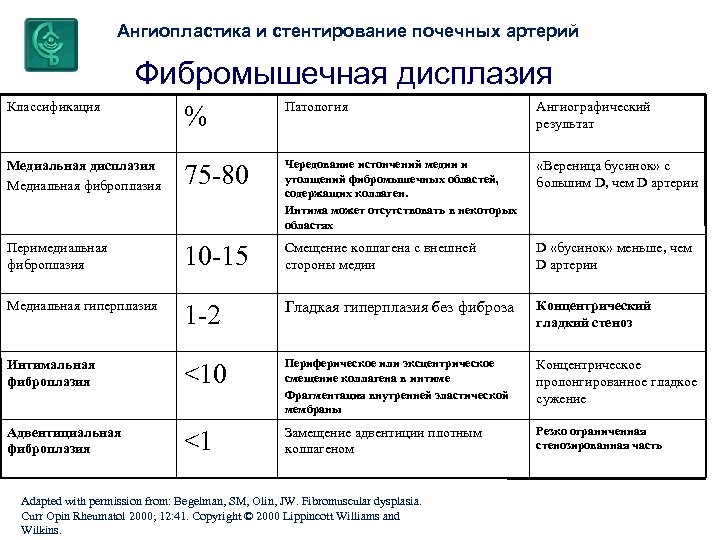

Ангиопластика и стентирование почечных артерий Фибромышечная дисплазия Классификация % Патология Ангиографический результат Медиальная дисплазия Медиальная фиброплазия 75 -80 Чередование истончений медии и утолщений фибромышечных областей, содержащих коллаген. Интима может отсутствовать в некоторых областях «Вереница бусинок» с большим D, чем D артерии Перимедиальная фиброплазия 10 -15 Смещение коллагена с внешней стороны медии D «бусинок» меньше, чем D артерии Медиальная гиперплазия 1 -2 Гладкая гиперплазия без фиброза Концентрический гладкий стеноз <10 Периферическое или эксцентрическое смещение коллагена в интиме Фрагментация внутренней эластической мембраны Концентрическое пролонгированное гладкое сужение <1 Замещение адвентиции плотным коллагеном Резко ограниченная стенозированная часть Интимальная фиброплазия Адвентициальная фиброплазия Adapted with permission from: Begelman, SM, Olin, JW. Fibromuscular dysplasia. Curr Opin Rheumatol 2000; 12: 41. Copyright © 2000 Lippincott Williams and Wilkins.

Ангиопластика и стентирование почечных артерий Фибромышечная дисплазия Классификация % Патология Ангиографический результат Медиальная дисплазия Медиальная фиброплазия 75 -80 Чередование истончений медии и утолщений фибромышечных областей, содержащих коллаген. Интима может отсутствовать в некоторых областях «Вереница бусинок» с большим D, чем D артерии Перимедиальная фиброплазия 10 -15 Смещение коллагена с внешней стороны медии D «бусинок» меньше, чем D артерии Медиальная гиперплазия 1 -2 Гладкая гиперплазия без фиброза Концентрический гладкий стеноз <10 Периферическое или эксцентрическое смещение коллагена в интиме Фрагментация внутренней эластической мембраны Концентрическое пролонгированное гладкое сужение <1 Замещение адвентиции плотным коллагеном Резко ограниченная стенозированная часть Интимальная фиброплазия Адвентициальная фиброплазия Adapted with permission from: Begelman, SM, Olin, JW. Fibromuscular dysplasia. Curr Opin Rheumatol 2000; 12: 41. Copyright © 2000 Lippincott Williams and Wilkins.